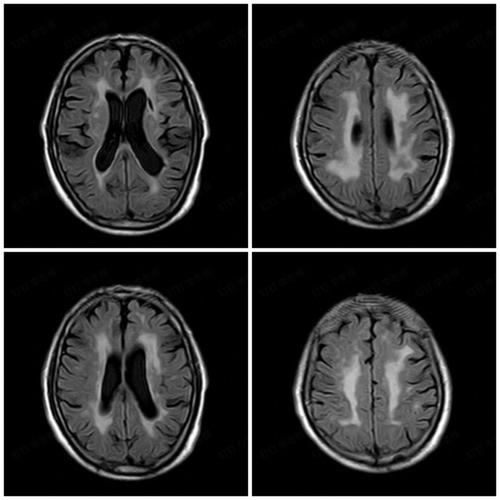

影像学表现: 在磁共振上,脑白质脱髓鞘病灶通常表现为T2加权像和FLAIR序列上的高信号,医生会根据病灶的形态、分布(如是否贴近脑室)、数量等来判断其可能的原因。